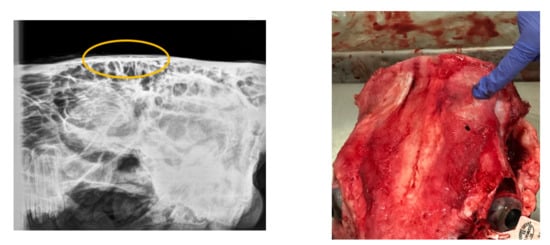

Regarding the radiographical study, it was observed that the skulls presented rating 1 “no visible damage” (70%) or 2 “indentation no cracking” (20%), and rating 3 “indentation with cracking but no displacement” (10%) following the Malaysia Standard (Figure 3, Figure 4, Figure 5). Consequently, 90% of the HSS animals (ratings 1 and 2) would be accepted for halal commercialization. However, no radiographical differences existed between ratings 1 and 2 (Figure 3 and Figure 4); only macroscopic differences in soft tissues were noted.

Figure 4.

Digital radiography rating 2 (following Malaysia Standard 1500:2009), and related photograph.